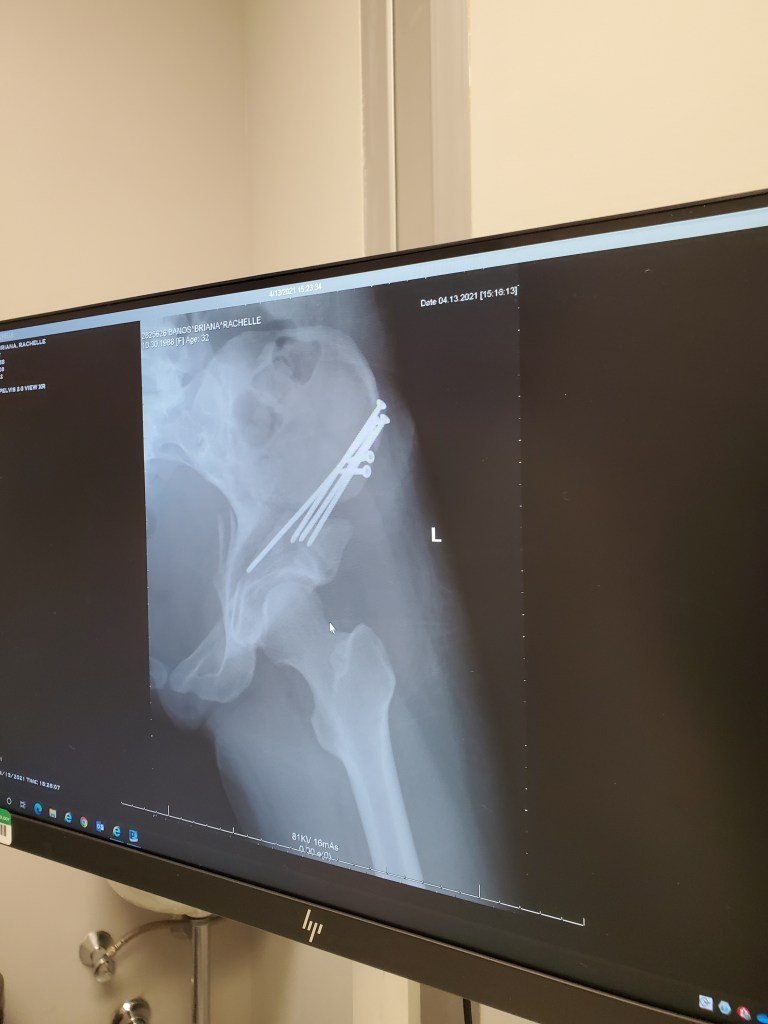

It’s now been 5 weeks since my first arthroscopy surgery and 3 weeks since my PAO surgery.

But let’s cut to the chase… who wants to see the money pics!! Screws and all!